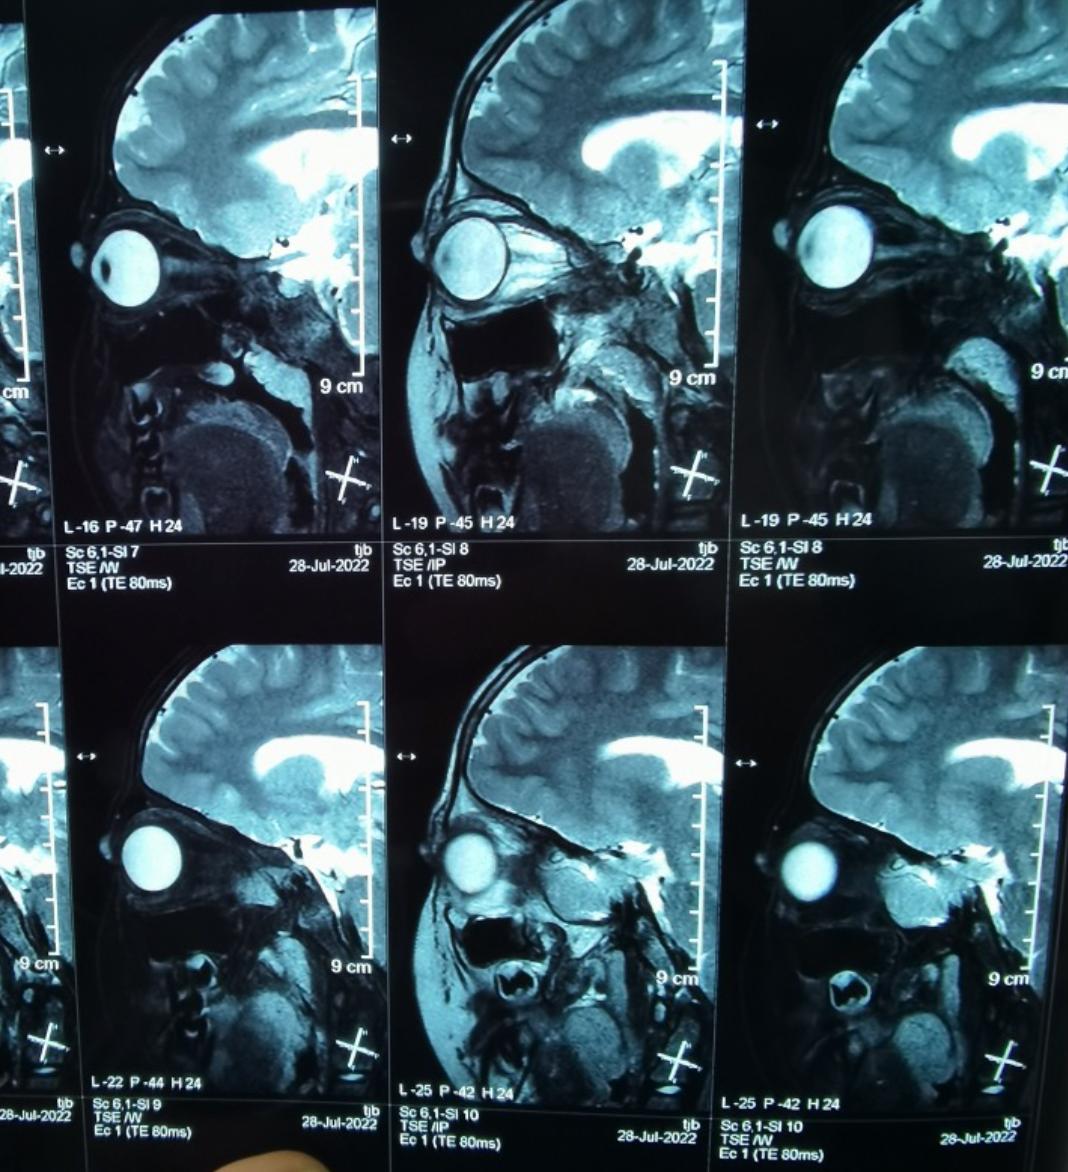

术前影像